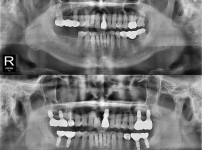

智齿拔除

完全埋伏智齿

조회